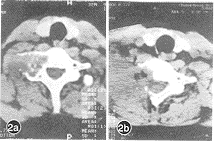

我们对2例生长于横突部的恶性肿瘤病人成功地作了矢状向颈椎半脊椎切除术。从侧方入路,兼处理椎体、横突、小关节、椎板病灶(图2,插Ⅳ),手术有相当难度,但大大增加了外科处理效果。

图2 C7右横突部软骨肉瘤矢状向半脊椎切除术患者CT片(2a 术前,2b 术后)